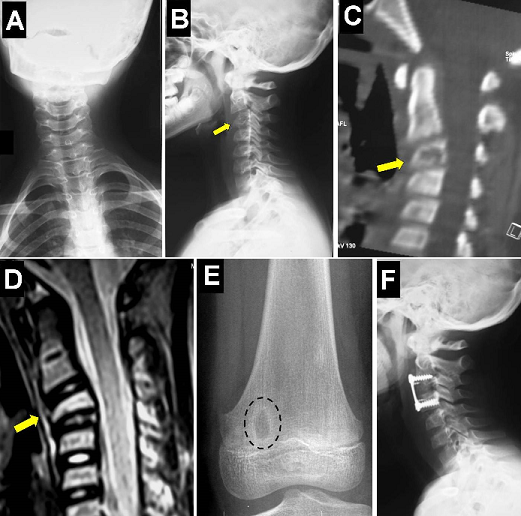

A 10-year-old boy presented with torticollis and neck pain for 2 months without fever. His physical examination showed torticollis and limitation of flexion/extension and cervical rotation without neurological deficit. Family and past histories were unremarkable. Cervical spine radiographs showed a cervical scoliosis with loss of the normal cervical lordosis and partial collapse of C3 vertebral body (A and B). Cervical computed tomography-scan and magnetic resonance imaging demonstrated a destruction of C3 vertebral corpus (vertebra plana) without discitis or spinal cord compression (C and D). A malignant bony tumor was suspected. Routine blood tests showed a mildly elevated erythrocyte sedimentation rate. Other skeletal X-rays revealed a well-defined solitary metaphyseal lytic lesion in the medial femoral condyle (E). An anterior cervical corporectomy was performed and the spine was stabilised with a tricortical iliac crest graft with plate/screws fixation (F). Histological features were consistent with eosinophilic granuloma. The patient was discharged home pain free with a good outcome. Eosinophilic granuloma (EG) is a benign and solitary bony lesion of unknown etiology. EG, Letterer-Siwe, and Hand-Schuller-Christian disease represent a spectrum of the same disease entity now known as Langerhans cell granulomatosis or histiocytosis X. EG predominantly affects the skull, the ribs, the pelvis, the mandible, and the metaphyses of other long bones. Although rare, EG should always be included in the differential diagnosis for osteolytic lesions of the spine in children.